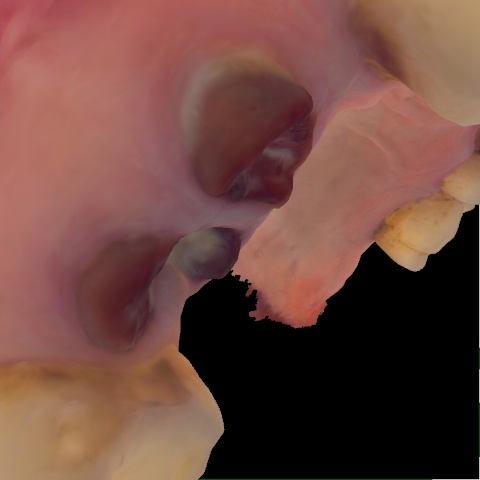

Incorrect Quality Level

The reference annotation for this image is

None

.

Please select the correct quality level.

Image 72 / 1743

Annotated as "Good"